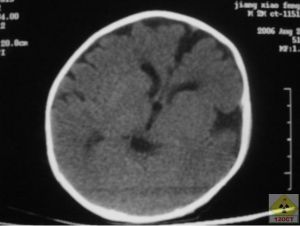

CT圖臨床表現

患病兒童1、縱裂接近三腦室前部(胚胎期縱裂與透明隔間腔相通,以後被胼胝體嘴封閉,若嘴不發育則縱裂與透明隔間腔相通,直達三腦室前部。嘴部發育最晚,無論胼胝體發育不全或不發育均累及胼胝體嘴部。所以縱裂與三室前部相通是最常見的表現。

3、側腦室前角向外移位,側腦室內側緣有凹陷的壓跡。原因是原先連線兩側半球的前部胼胝體缺如,那些本來橫向連線兩側半球的纖維現在呈縱向排列,位於側腦室內緣,壓迫側腦室,形成壓跡。畸形的兩側腦室前角彼此分離,形成蝙蝠翼狀。

4、側腦室體分離,相互平行,主要見於橫斷面圖象上,可能是輕度胼胝體發育不全僅有的表現。

5、胼胝體壓部缺如,使側室三角區擴大。

8、第三腦室位置升高,並呈囊狀擴張,使兩側大腦內靜脈分離。